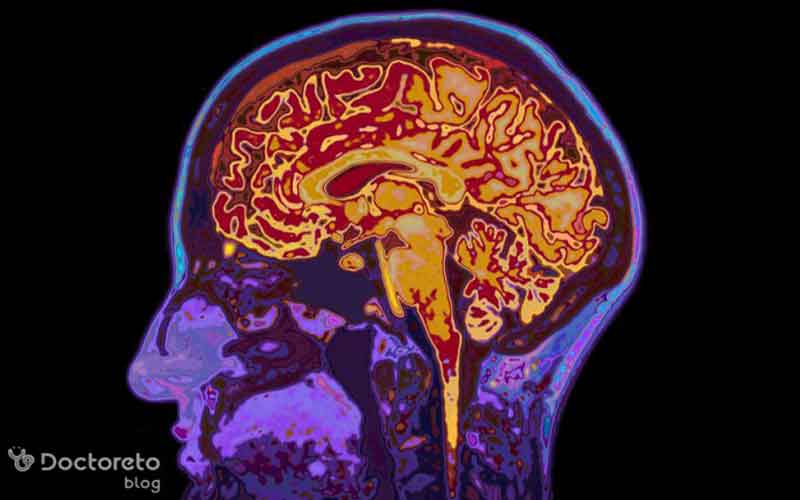

تشخیص فلج شدن بعد از جراحی تومور مغزی بر پایه بررسیهای بالینی و آزمایشهای تخصصی انجام میشود. دکتر مغز و اعصاب ابتدا با معاینه عصبی علائمی مانند ضعف یا عدم حرکت اندامها، کاهش رفلکسها، مشکلات تعادلی و تغییرات در گفتار یا بینایی را ارزیابی میکند. همچنین ارزیابیهای شناختی برای بررسی توجه، حافظه، سرعت پردازش اطلاعات و عملکرد اجرایی بهکار گرفته میشود. در کنار این موارد، از روشهای تصویربرداری مانند MRI یا CT اسکن هم برای بررسی تورم، خونریزی یا آسیب به نواحی حرکتی مغز استفاده میشود.